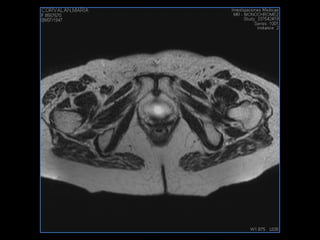

PROTOCOLO pelvis SAG T2, Y FAT SAT (FINOS) AXIAL T1  AX FAT SAT CON   GADOLINIO :  AX T1 Y COR T1 SAT: NO  FASE: RL THK: 3MM  COIL:  GAP: (FACTOR 1.4) 1MM FOV: 40 CM NEX:2 SINCRONIZACION RESPIRATORIA EN 3 O 4 CICLOS ALE

resonancia de abdomen